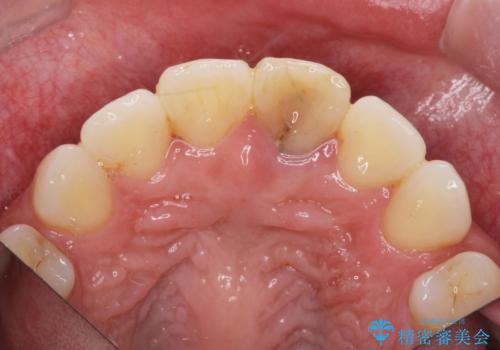

- 神経の治療をしたまま放置していた歯が、変色してきたので改善したい。と前歯の審美性の改善を求めて来院されました。

根管治療後の歯には部分的な修復処置が為され、変色が進行している状態でした。

ジルコニアクラウンを用いて、自然な色調となるよう治療を計画します。

根管治療は行わず、仮歯・ジルコニアクラウンのみの処置を行い自然な歯に仕上げることができました。